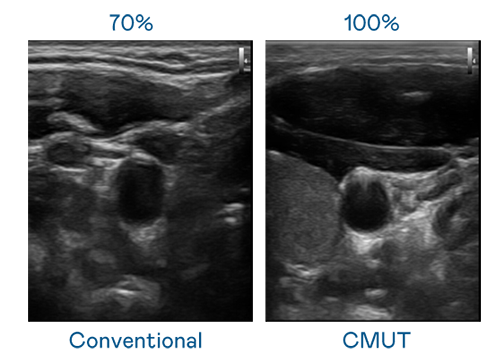

CMUT 技术是一种用电容式微机电元件来产生超音波讯号的技术。与传统 PZT 压电式技术相比,CMUT 频宽增加 30%,更宽频的超音波讯号让影像解析度大幅提升,是实现高影像品质医疗超音波扫描、促进精准医疗发展的关键技术。

大频宽带来超清晰影像

超音波影像的解析度高低,首先取决于探头能发出的讯号频宽。环球360 CMUT 可提供高清晰的超音波讯号,提供高频宽、高灵敏度、影像纹理细节更高的超音波影像,协助医护人员缩短影像判读时间及利用精准的医疗影像进行诊断。